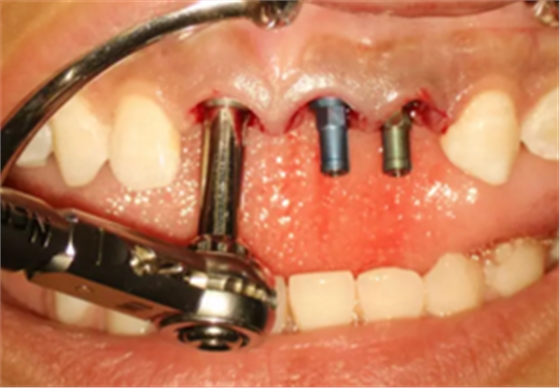

(2)即刻种植、即刻临时修复。术中不翻瓣微创拔除牙根,牙槽 窝骨壁完整。在多级导板辅助下完成种植窝洞制备,植入Bego柱形种植 体,型号分别为:上颌右侧中切牙位点4.1mm×15mm、上颌左侧中切牙 位点?3.75mm×15mm、上颌左侧侧切牙位点3.25mm×15mm,扭矩均为 35N·cm。种植体与唇侧骨壁间隙约2mm,植入Bio-Oss®Collagen骨胶 原。戴入桥用钛临时基台,临时冠就位顺利,自凝树脂口内粘接后适当修整 外形,充分磨光,调 至正中 、前伸 和侧方 与对颌牙均无接触。术后 根尖片显示种植体位置、方向良好。

图9 植入种植体